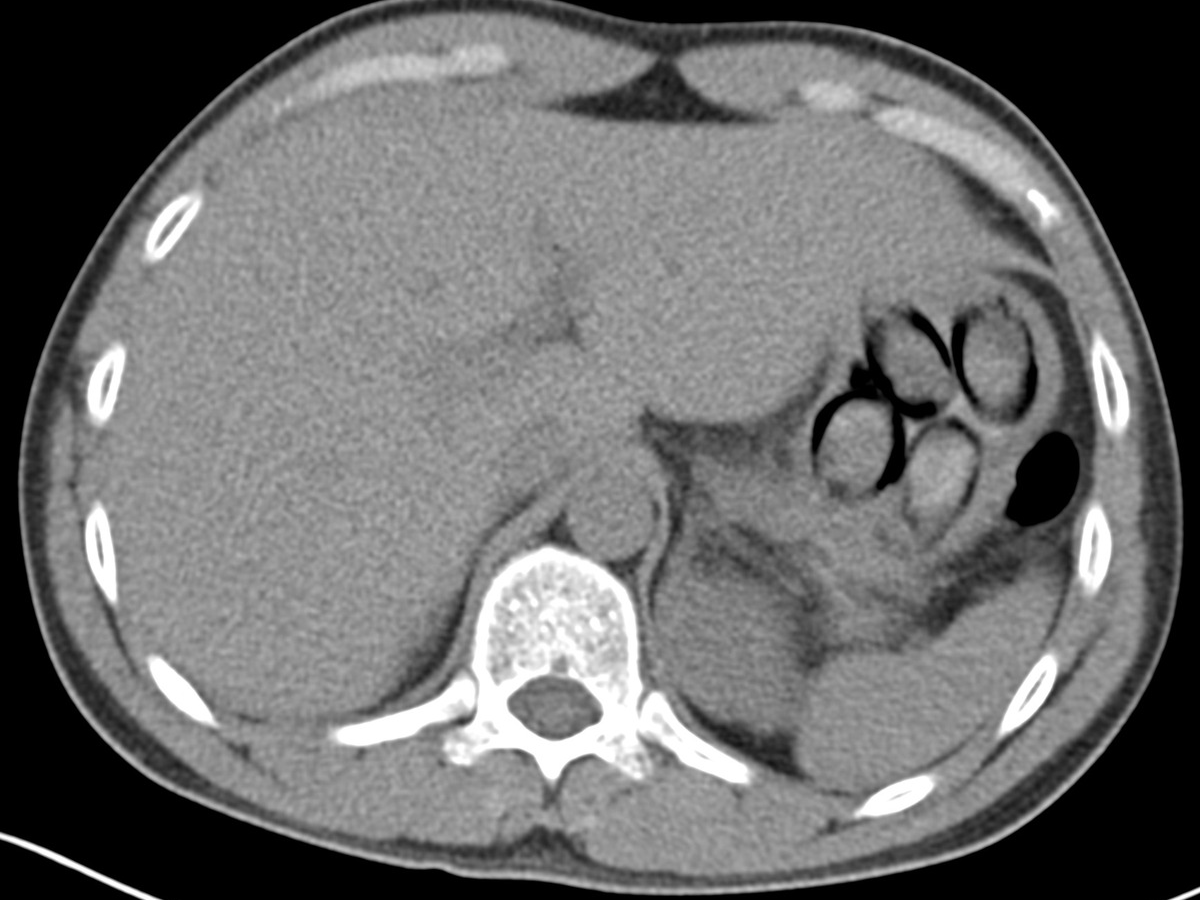

"Die Röntgenaufnahme in einem nahegelegenen Krankenhaus bestätigte letztendlich den Verdacht meiner Kolleginnen und Kollegen, denn im Magen des Mannes waren mehrere Drogenpäckchen klar zu erkennen. Insgesamt schied der Mann dann unter Überwachung sieben sogenannte Bodypacks mit insgesamt mehr als 100 Gramm Kokain aus", so Jens Ahland, Pressesprecher des Hauptzollamts Köln.